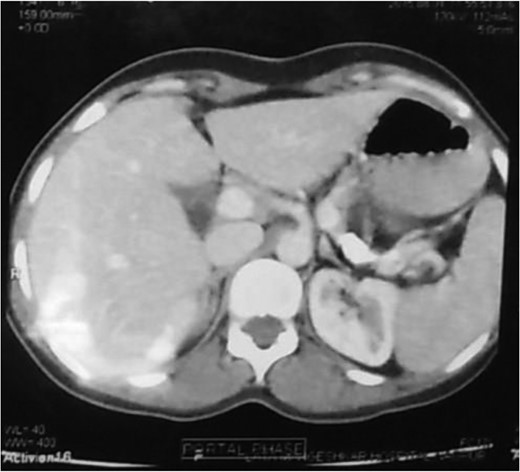

CT scan showing multiple conglomerated calcifications at the tail of pancreas.